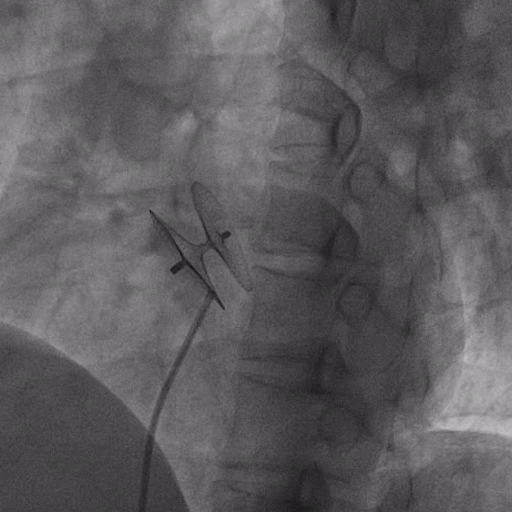

在獲得患者同意后,1月12日,尚福軍主任為患者進(jìn)行了PFO封堵術(shù)。術(shù)中造影可見(jiàn)封堵器殘余漏,尚福軍主任用精湛的技藝,順利通過(guò)封堵器殘余漏裂縫,將右心導(dǎo)管從右房送入左房,且順利到達(dá)肺靜脈;遂行卵圓孔未閉封堵術(shù)后殘余漏再次封堵;且完美釋放PFO封堵器,可見(jiàn)兩封堵器呈“馬蹄蓮”狀,再次術(shù)中造影未見(jiàn)殘余漏。

術(shù)后,小鞏生命體征平穩(wěn)。相關(guān)檢查顯示正常,且術(shù)后完善心臟彩超及發(fā)泡試驗(yàn),可見(jiàn)封堵器位置良好,未見(jiàn)右向左分流,發(fā)泡試驗(yàn)陰性。